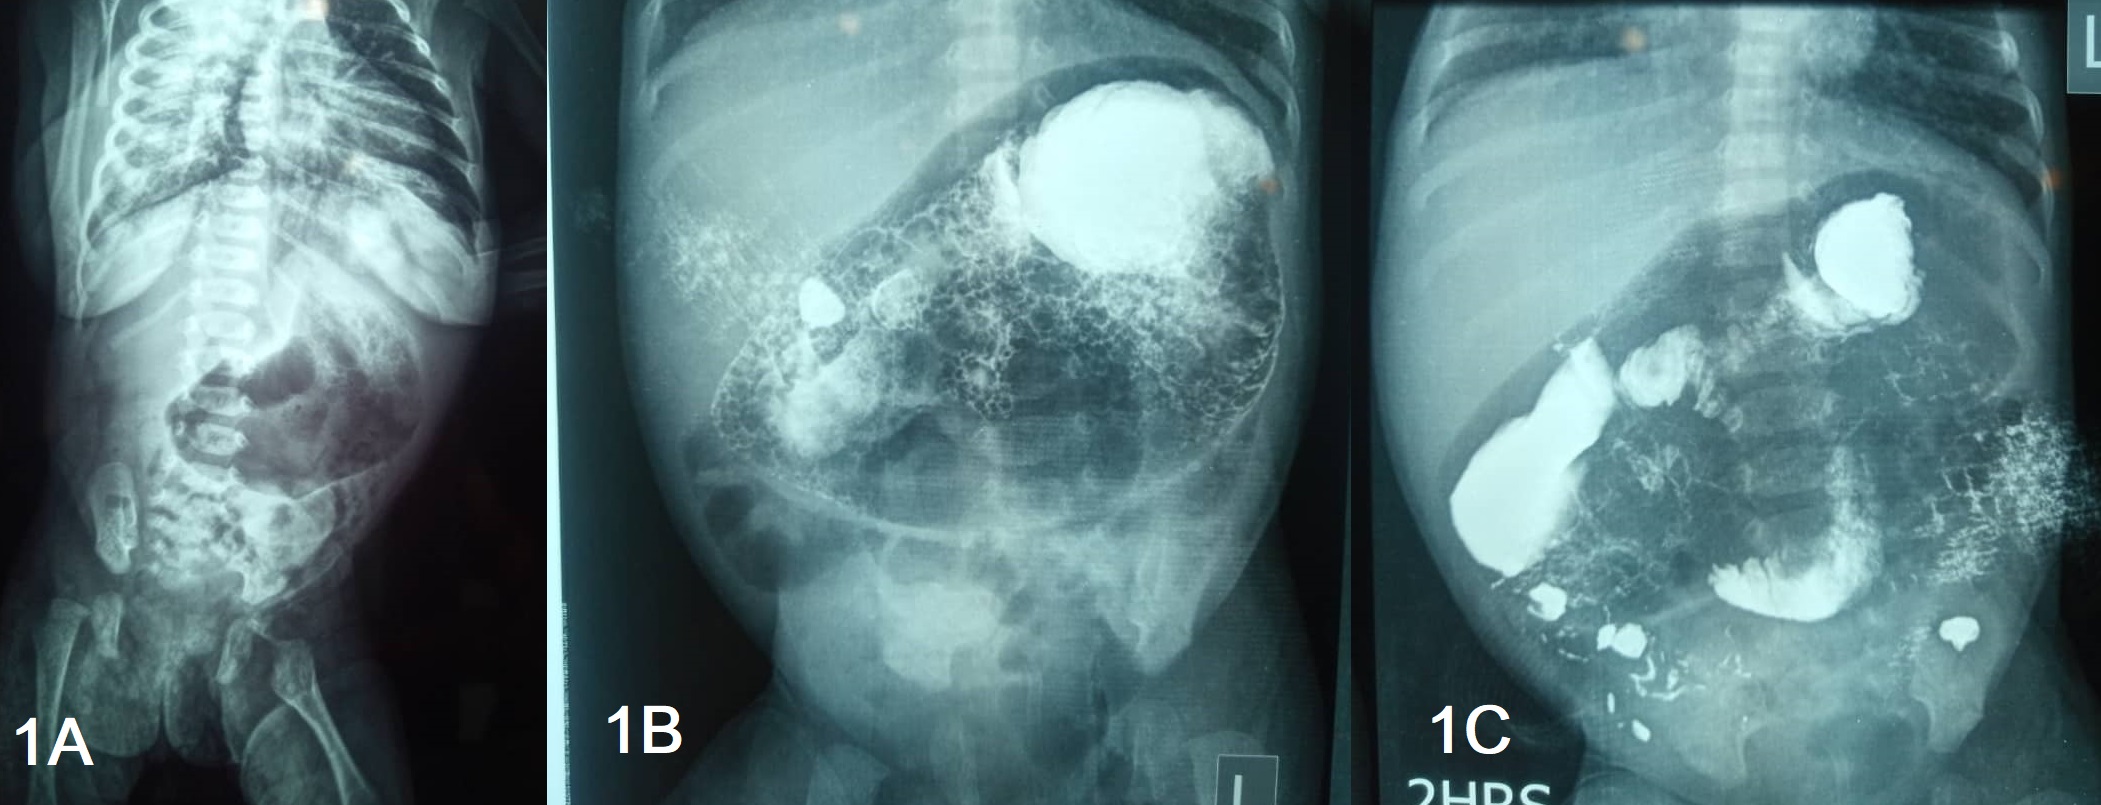

Plain abdominal x-rays showed a grossly dilated stomach and paucity of gas in the distal bowel (Fig. 1A). Abdominal distension resolved after 2 days while NGT drainage became clear and the baby started passing stools. He was allowed dextrose water via NGT which was tolerated for 5 days before the residual became bilious again.

The upper GI series suggested dilated stomach and proximal duodenum up to the third part; there was delayed passage of minimal contrast distally (Fig. 1B, 1C). The abdominal ultrasound was unremarkable due to the gaseous distension.

Imaging studies are mostly inconclusive. [9] Plain abdominal x-rays may be unremarkable, or it may also show dilated stomach and proximal bowel, there may be a paucity of gas in the distal bowel, or crowding of small bowel gas shadows. [5], [7] If there are no signs of complete obstruction, contrast gastrointestinal x-ray series may show delayed intestinal transit time. However, no definite transition point is usually seen. Abdominal ultrasound has been reported to show a cauliflower sign depicting the encased bowel on a stalk of its narrow mesentery base. This is usually obscured if there is proximal dilatation and excess intraluminal gas but may be more prominent in the presence of ascites.[7], [11] In adults, a contrast-enhanced CT scan may be the best option for investigating suspicion of an abdominal cocoon but the risk of exposure to such high doses of radiation, makes it unattractive in neonates.

A) Plain abdominal radiograph showing grossly dilated stomach and paucity of gas in the distal bowel, B and C) Barium meal and follow-through showing dilated stomach and duodenum and jejunum